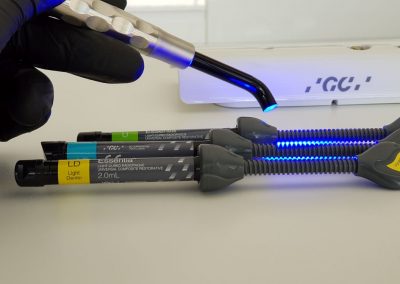

PROPHY JET sau AIR FLOW

– dispozitiv ce proiecteaza un jet controlat de apa, aer si microparticule de bicarbonat de sodiu cu diferite arome fructate, pe suprafata dintilor si in zonele interdentare mai greu de igienizat. Este indicat ca tratament complementar in sedintele de profilaxie si de asemenea la igienizarea periodica a lucrarilor si implanturilor dentare, in ortodontie la aplicarea si iginizarea bracket-urilor, iar la copii pentru pregatirea dintilor in vederea sigilarii.

OBTURATIE

– este probabil cel mai comun tratament dentar (plomba in termeni populari). Este de fapt o metoda de reconstructie a unui dinte deteriorat de carii pentru ai reface forma si functionalitatea. De mentionat ca obturatia unei suprafete a dintelui nu este acelasi lucru cu obturarea si tratarea canalului radicular (adica radacina dintelui), aceste doua manopere fiind total diferite.